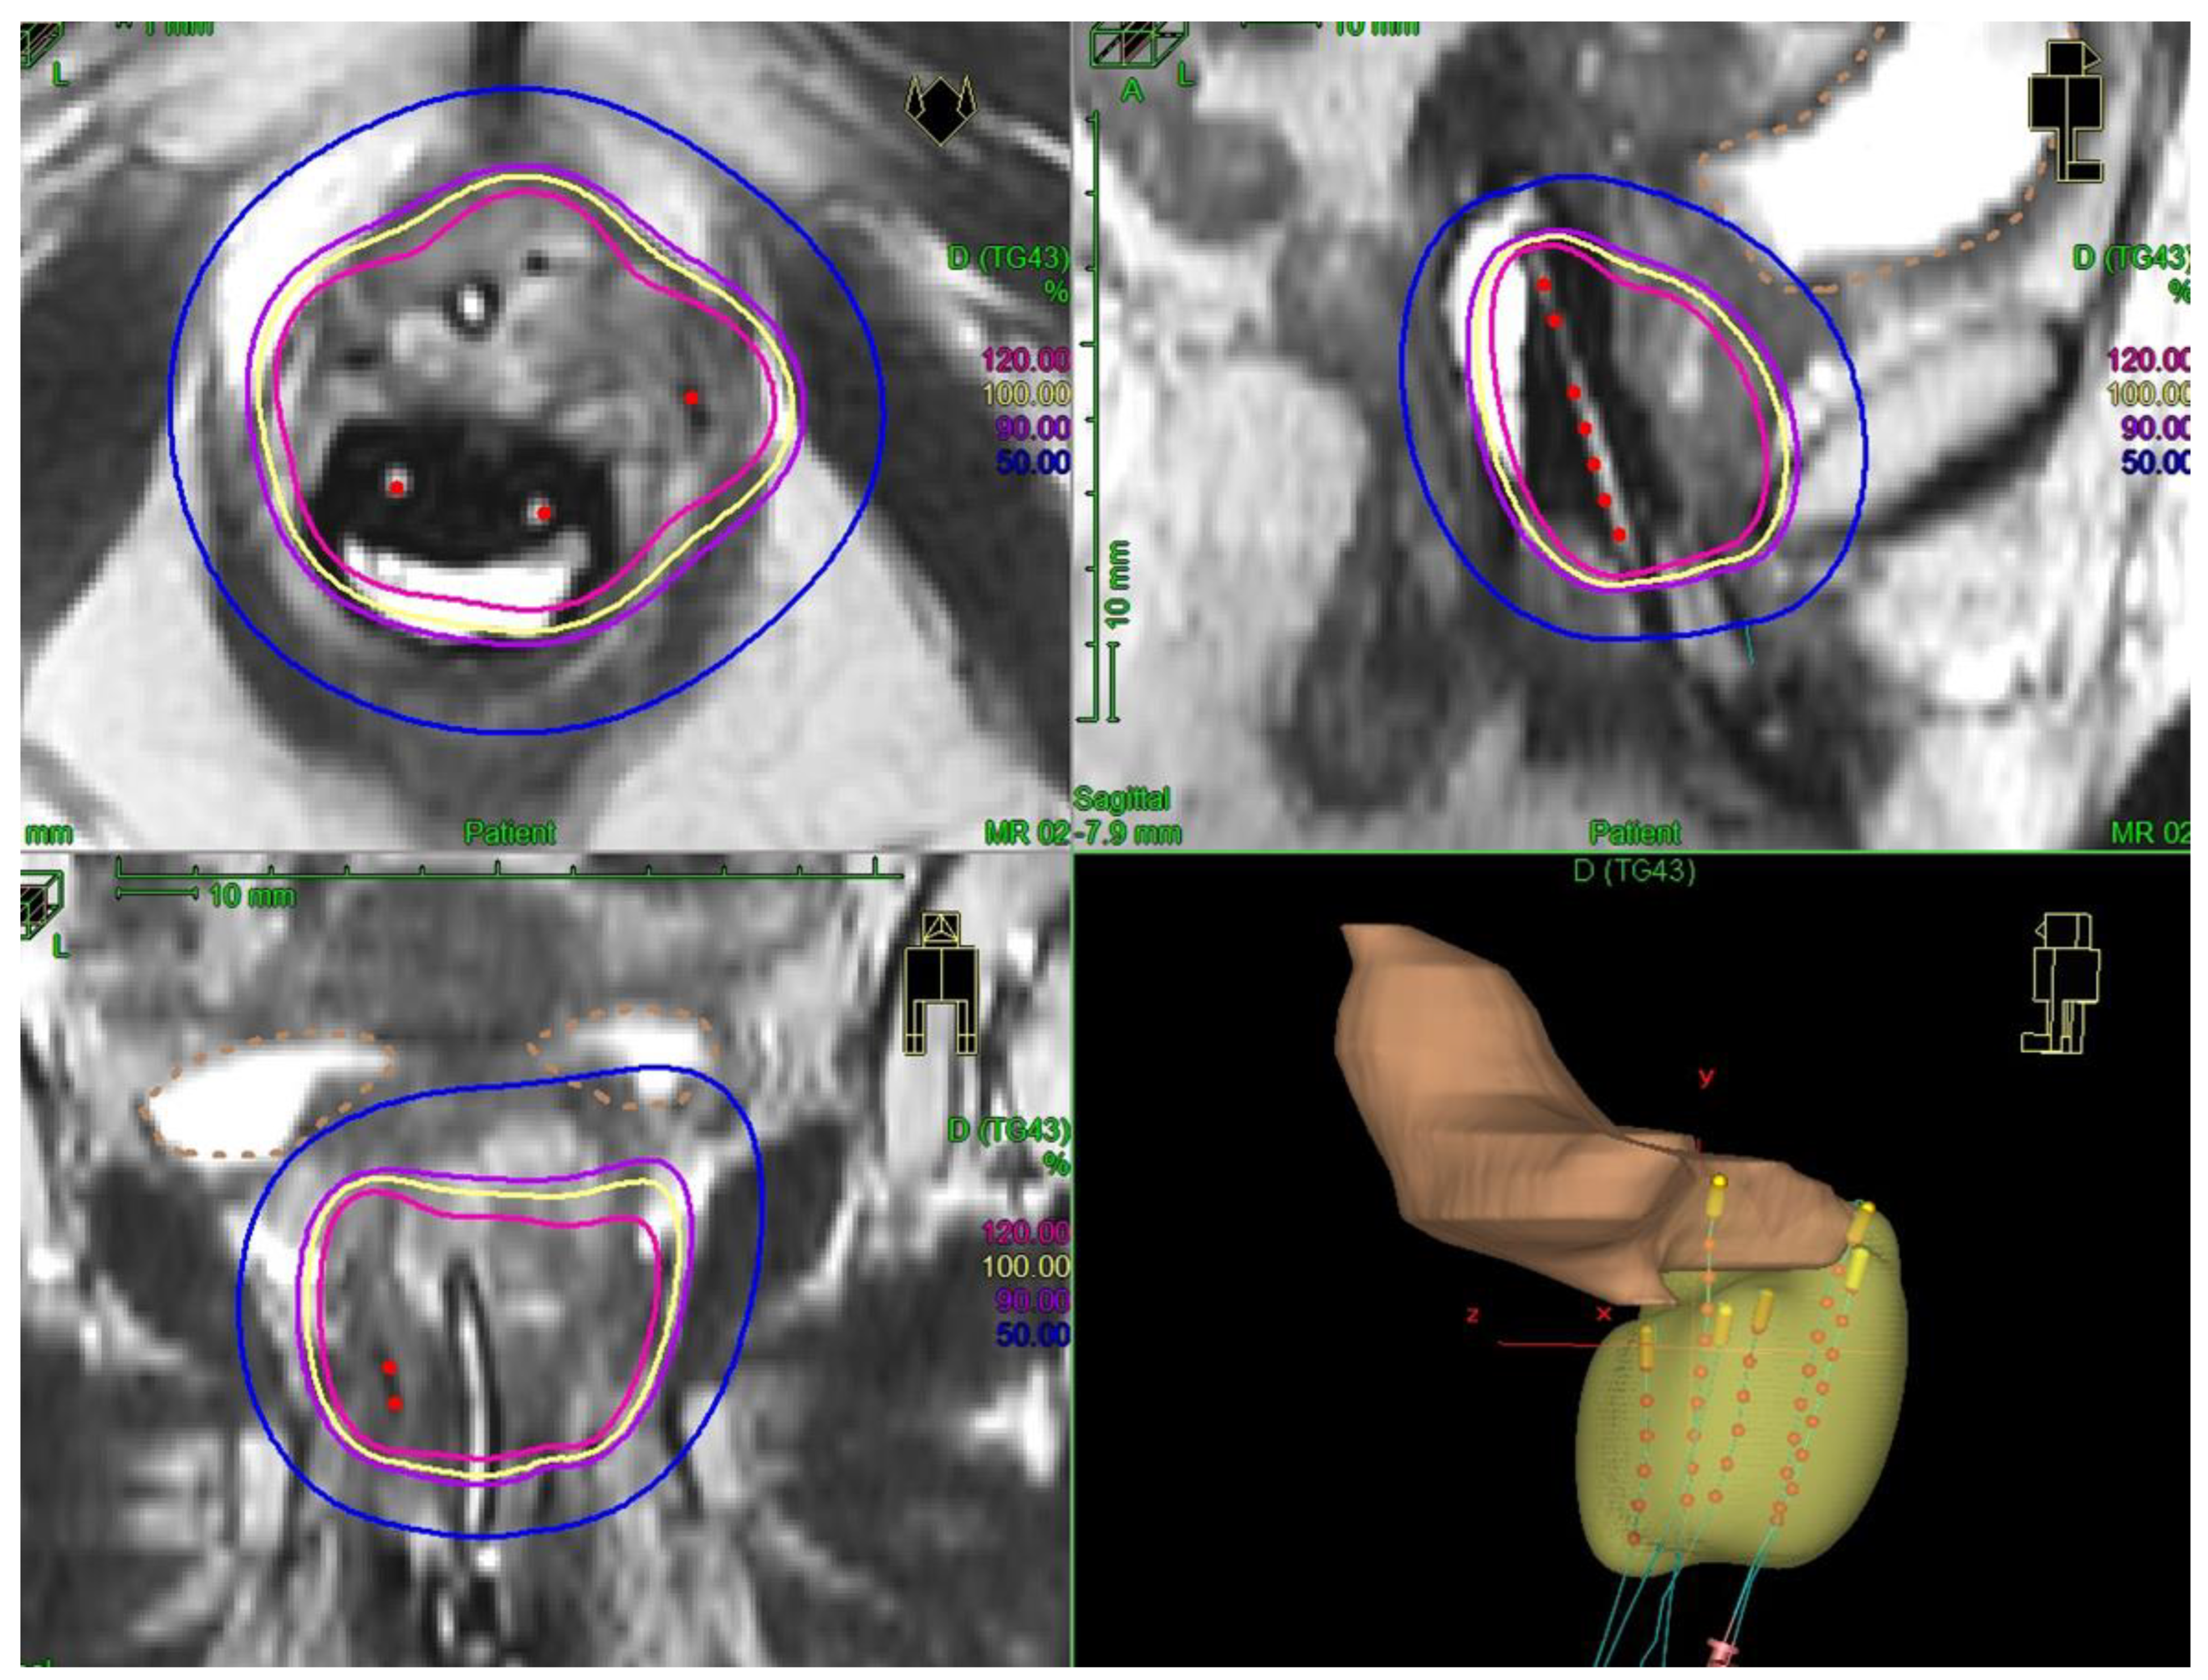

For all patients, a personalized vaginal mold applicator was built from a vaginal impression to adapt the number and positions of the brachytherapy catheters according to the tumor shape and extent. Brachytherapy implant was performed under general anesthesia, allowing a careful gynecological examination to decide on the implant geometry. Transperineal free-hand interstitial needles were implanted for patients with a tumor thickness of more than 7 mm. At the time of implant, fiducial seeds could be implanted to visualize tumor extents on radiographs or CT. Before 2014, treatments were delivered through continuous low-dose-rate (LDR) brachytherapy. Thereafter, treatments were delivered through pulse-dose-rate (PDR) technology. For patients treated at the time of LDR brachytherapy, brachytherapy treatment planning was based on 2D radiographs. For patients treated with PDR, 3D imaging (MRI and/or CT) was performed with an applicator in place. Clinical target volumes were defined according to clinical and radiological findings. For patients treated with brachytherapy as a boost, a brachytherapy dose of 15–20 Gy was prescribed, with the objective to deliver a total dose of at least 60 Gy to initial sites of disease (clinical target volume = CTV), taking into account the contribution of external beam radiotherapy and with dose escalation at the level of residual disease (residual gross tumor volume at the time of brachytherapy = GTV). For patients treated with exclusive brachytherapy, the objective was to deliver at least 70 Gy to the macroscopic tumor (GTV) and 60 Gy to the tumor plus a 3D anatomical margin of 5–10 mm (CTV). No dose constraint was applied for the urethra that could be part of the target volume. For applications performed before 2014, Cesium-137 was used for intracavitary applications and Iridium-192 wires were used as interstitial sources. After 2014, pulse-dose rate brachytherapy was used and stepping source Iridium-192 was used for both intracavitary and interstitial treatments. An example of 3D treatment planning for a periurethral adenocarcinoma is shown in Figure 1.

Our study, including 50% primary para-urethral tumors and 50% para-urethral relapse, aims at providing additional data on this rare clinical presentation and examining the possibility to perform a conservative treatment. We report a local control probability of 80% at 2 years, comparable to previously described data. With a higher number of patients, we show that good local control can be achieved with brachytherapy either for primary tumors or for the treatment of para-urethral recurrences of pelvic tumors. OS at 2 years was 63%, also in line with previously described data, with distant failure being the main pattern of relapse. In our series, the distant failure probability was reported in 45% of patients, highlighting the need for systemic intensification in these patients. In addition, 25% of patients had relapse from endometrial cancer, and at the time of study molecular profiling was not done on a routine basis. This may contribute to the high frequency of distant failures in these patients. The prognosis was poorer than in cervical cancer or than reported in other series of primary vaginal tumors. First, local control was lower, probably because dose escalation was limited given the higher risk of necrosis compared to other tumors located in the upper part of the vagina or developed from the cervix. Second, almost half of the patients had a previous history of pelvic radiotherapy, precluding delivering a prophylactic pelvic lymph node irradiation, possibly explaining the high frequency of distant events. Finally, half of the patients were referred for locoregional relapse. Although the safety profile was acceptable, we observed four cases of focal vaginal necrosis, predominantly in the group treated before 3D imaging and stepping source technology use. Among the two patients with available information concerning the treated volume, the brachytherapy V100% was very large in both of them (>150 cm3). Dose and volume have a major impact on severe toxicities for brachytherapy treatments, though data in this specific clinical situation are still uncertain and our study does not allow drawing definitive conclusions on dose/volume parameters, given the low number of patients with available 3D dosimetric data [19,20]. No urethral dose constraint was followed. One specificity for para-urethral tumors is that the urethra can be part of the target volume (if initially involved) but is also an organ at risk. Contrary to prostate cancers, where urethra is usually not involved, there can be very close contact between the urethra and gynecological tumors, and therefore the urethra could be included as part of CTV (Figure 1). A prospective EMBRAVE study will collect clinical and dosimetric data for patients with primary vaginal tumors. This study should provide meaningful information in terms of dose/effects relationship for dosimetric optimization guidance.

Figure 1. Example of image-guided pulse-dose-rate treatment for a primary para-urethral carcinoma. Patient was treated with pulse-dose-rate brachytherapy boost, delivering 15 Gy in pulse-dose-rate brachytherapy. In yellow is shown the 100% isodose. A vaginal mold applicator with anterior catheters was used and three interstitial needles were implanted to encompass the urethra.